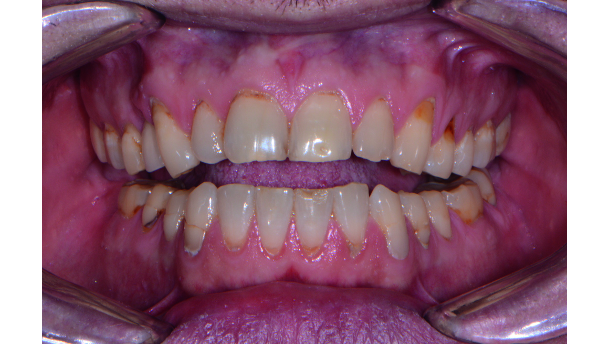

A man in his late 30s was referred to my practice by his dental provider because he was dissatisfied with the appearance of his smile. The patient commented that he felt that his existing teeth and restorations were unattractive because of recurrent decay, wear and colour (Figs. 1 & 2). Most importantly, he mentioned that he was suffering from tension headaches, grinding and a limited range of function.

Initial diagnostic evaluation at the first appointment consisted of a series of digital images with study casts, a centric relation bite record, a face bow transfer and a full mouth set of X-rays. In the maxillary arch, the patient had several teeth that had worn composite restorations as well as abfractions with cervical decay. Tooth #5 had an existing crown on an implant.

In the lower arch, several existing composite restorations had wear as well as decay on the facial cervical areas. Although there were no re storations present in the anterior mandibular teeth, there was severe wear in the incisal edges due to possible grinding, parafunction and end-to-end bite.